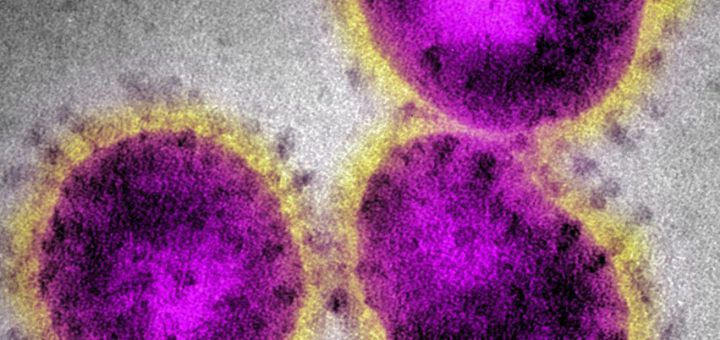

0 普通のニュース 2021/6/10 木曜日 by くまさん · Published 2021/6/10 木曜日 インドで確認の変異ウイルス 感染力は従来ウイルスの1.78倍か 今はデルタ株とか言うらしい アルファだベータだって,どのコロナバージ...

0 普通のニュース 2021/5/30 日曜日 by くまさん · Published 2021/5/30 日曜日 【#ベトナム変異株】「おいおい、ラスボス登場かよ」新たにベトナム変異株発見 乙武氏も衝撃 混ぜるな危険,キタ━(゚∀゚)━!! イギリス株とインド株のミックス...

0 普通のニュース 2021/5/16 日曜日 by くまさん · Published 2021/5/16 日曜日 【#新型コロナ】台湾で新たに207人感染(21/5/16) 鉄壁を誇った台湾が陥落したヤバス 変異株ヤバすぎやろ.台湾,あっとい...

0 普通のニュース 2021/4/29 木曜日 by くまさん · Published 2021/4/29 木曜日 【#新型コロナウイルス】宮崎県:変異株が+26人(21/4/29) 宮崎も一挙に変異株が増えてキタ――(゚∀゚)――!! いきなり26人...